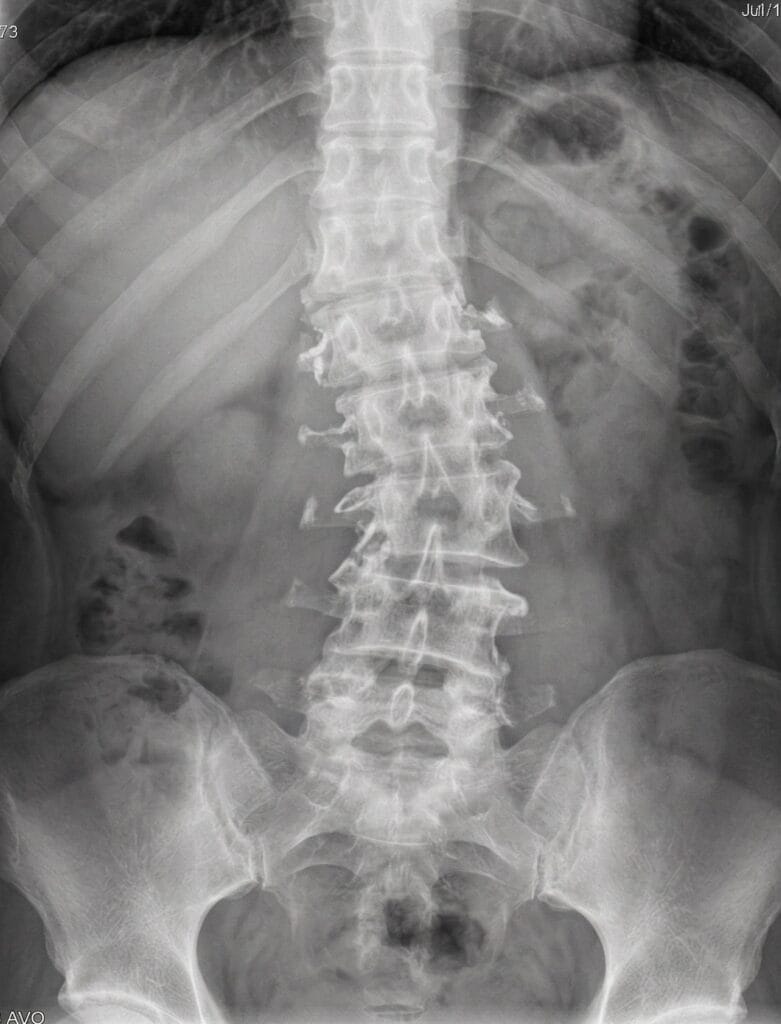

- We start by meticulously analyzing your X-rays to determine the exact angles of the curve and the direction of the vertebral rotation.